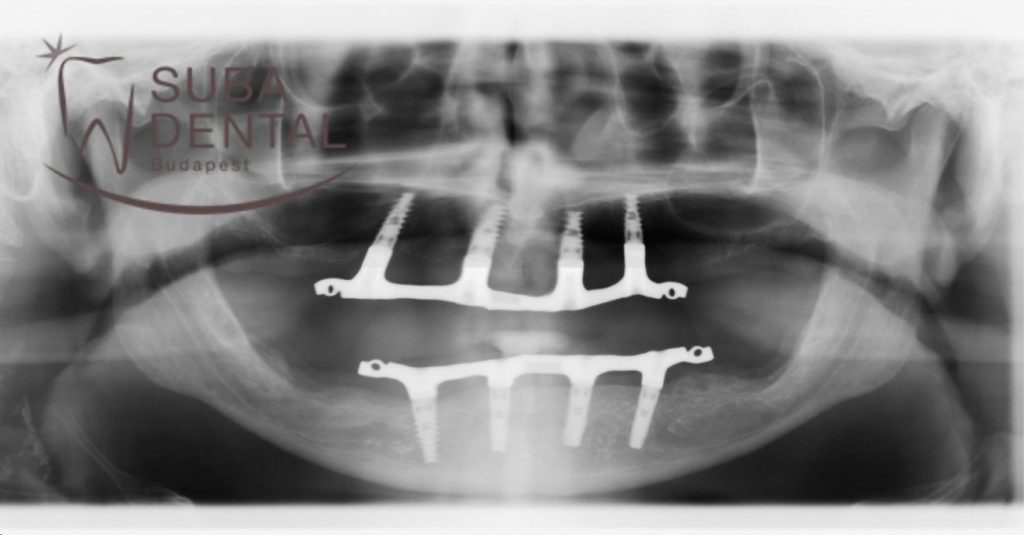

Az alsó és felső stégről készült kontroll panorámaröntgen-felvétel